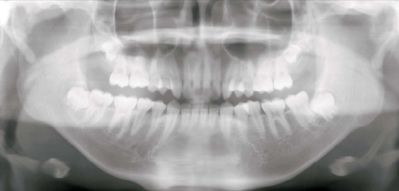

15 歳の男子。口を開けづらいことを主訴として来院した。5年前に気付き、徐々に開きにくくなったという。顎関節部に雑音や痛は認められない。最大開口量は 20 mm であった。初診時のエックス線画像とCT 横断像、矢状断像および 3D-CT 像を別に示す。

診断名はどれか。1つ選べ。

e. 筋突起過長症